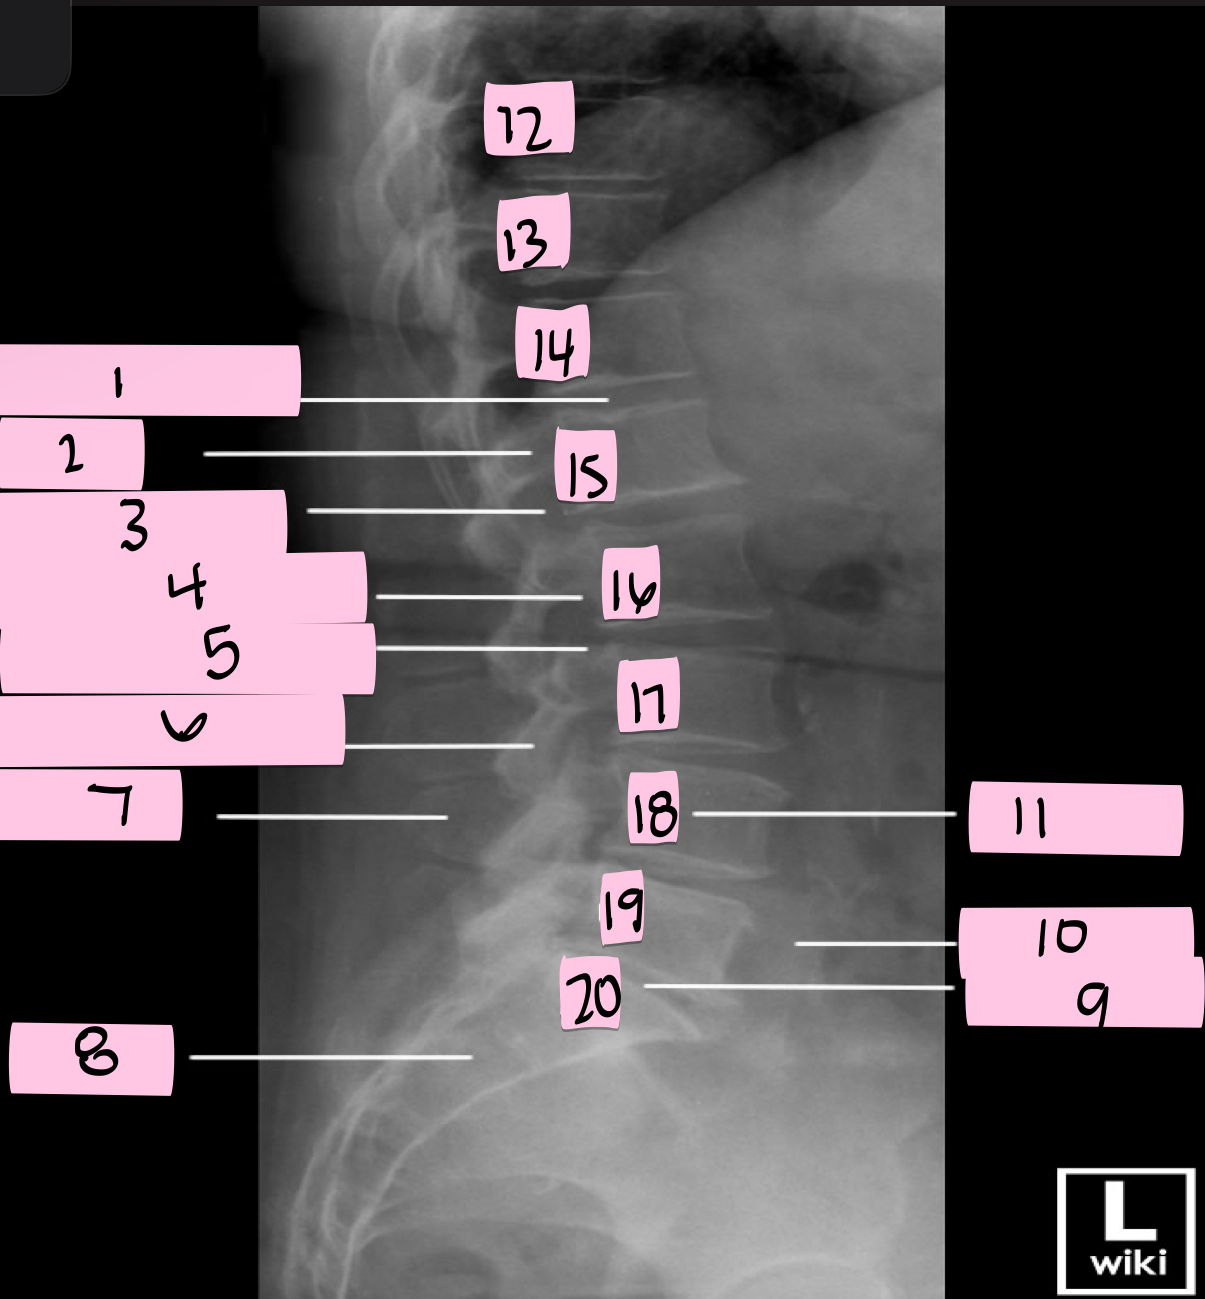

What is 1 pointing to?

Intervertebral disk

What is 2 pointing to?

Pedicle

What is 3 pointing to?

Intervertebral foramen

What is 4 pointing to?

Inferior vertebral notch

What is 5 pointing to?

Superior vertebral notch

What is 6 pointing to?

Inferior articular process

What is 7 pointing to?

Spinous process

What is 8 pointing to?

Sacrum

What is 9 pointing to?

L5 S1 joint

What is 10 pointing to?

Iliac crest

What is 11 pointing to?

Vertebral body (L4)

What is 12 pointing to?

T10

What is 13 pointing to?

T11

What is 14 pointing to?

T12

What is 15 pointing to?

L1

What is 16 pointing to?

L2

What is 17 pointing to?

L3

What is 18 pointing to?

L4

What is 19 pointing to?

L5

What is 20 pointing to?

S1